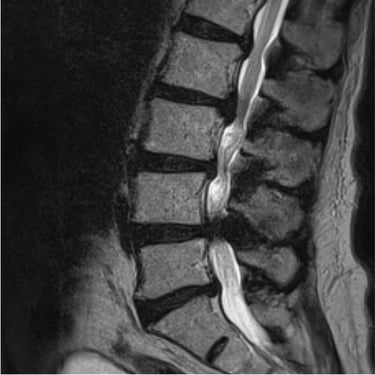

La listesis L4–L5 asociada a estenosis lumbar severa se caracteriza por el deslizamiento vertebral y el estrechamiento del canal espinal, generando dolor lumbar, claudicación neurogénica y compromiso radicular. Cuando el tratamiento conservador no logra un control adecuado de los síntomas, la fijación transpedicular (FTP) asociada a la fusión intersomática transforaminal (TLIF) constituye una alternativa quirúrgica eficaz. Este procedimiento permite descomprimir las estructuras nerviosas, restaurar la alineación vertebral y proporcionar una estabilización sólida del segmento afectado, favoreciendo una recuperación funcional segura y una mejor calidad de vida.